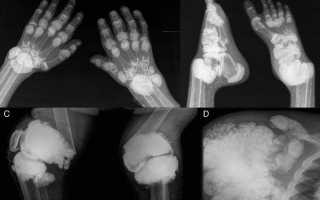

Поскольку крепкие напитки могут вызывать привыкание, пациент начинает употреблять их в большом количестве. Излишек МК откладывается в организме в виде камней и тофусов. Результаты негативного воздействия алкоголя на организм проявляются через некоторое время, поначалу процесс протекает практически бессимптомно. Чем больше пациент принимает крепкого алкоголя, тем болезненнее будет протекать подагра.

Водка нарушает почечную деятельность. Снижается выделительная функция органа, почки перестают целиком выводить излишек мочевины. Почечная недостаточность способствует росту концентрации уратов. Достаточно пагубное влияние водки на печень провоцирует проблему с выполнением ею антитоксической функции.

Так как водка быстро вызывает у людей привыкание, постепенно ее количественное употребление растет. Излишки уратов натрия откладываются внутри тканей, образуя камни либо тофусы. Подобное негативное воздействие водки далеко не моментально возникает. Патологические процессы постепенно и внешне незаметно прогрессируют. Чем дольше происходит злоупотребление водкой либо иными крепкими жидкостями, тем сильнее и гораздо чаще будут происходить подагрические атаки.